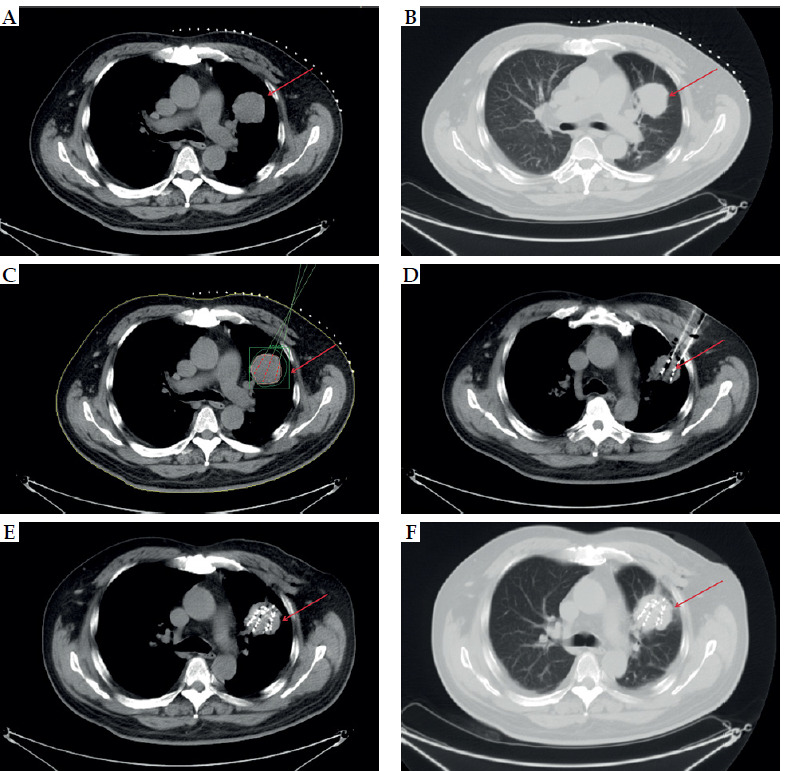

Purpose: This study aimed to explore the risk factors associated with difficult-to-control pain (visual analog scale [VAS] score > 3) experienced by patients with advanced non-small cell lung cancer (NSCLC) assessed at two months after receiving iodine-125 (125I) radioactive seed implantation combined with chemotherapy, in order to improve pain management and enhance patient quality of life.

Material and methods: A total of 87 patients diagnosed with advanced NSCLC were included in the study, all of whom underwent treatment using 125I radioactive seed radiotherapy and chemotherapy. Through univariate and multivariate analyses, the risk factors affecting pain control at two months post-treatment were identified. Predictive and survival analyses were done using ROC curves and Kaplan-Meier survival curves.

Results: The results indicated that minimal pleural distance, smoking history, and pleural effusion were independent risk factors influencing the control of pain shown in VAS scores. Moreover, a non-linear relationship between minimal pleural distance and difficulty of pain control was observed, indicating that the risk of uncontrolled pain decreases when the minimal pleural distance reaches ≥ 10.84 millimeters. ROC curve analysis demonstrated that the predictive capability of minimal pleural distance was the highest.

Conclusions: Minimal pleural distance, smoking history, and pleural effusion are significant factors in predicting the difficulty of pain control in patients with advanced NSCLC receiving 125I radioactive seed implantation combined with chemotherapy at two months post-treatment. Patients with a minimal pleural distance of less than 10.84 millimeters are more likely to experience uncontrolled pain after treatment. Therefore, developing predictive models may assist clinicians in more accurately evaluating treatment efficacy and patients' pain management needs.